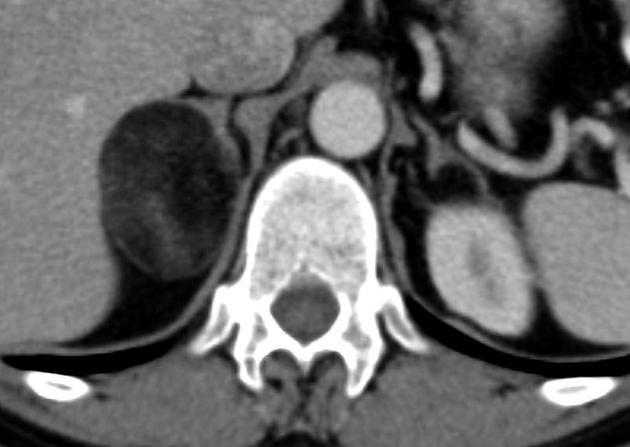

Diagnosis?

Differential?

Retroperitoneal liposarcoma.

Could also consider extrarenal angiomyolipoma. This would be more likely to have large vessels within the mass than liposarcoma is.